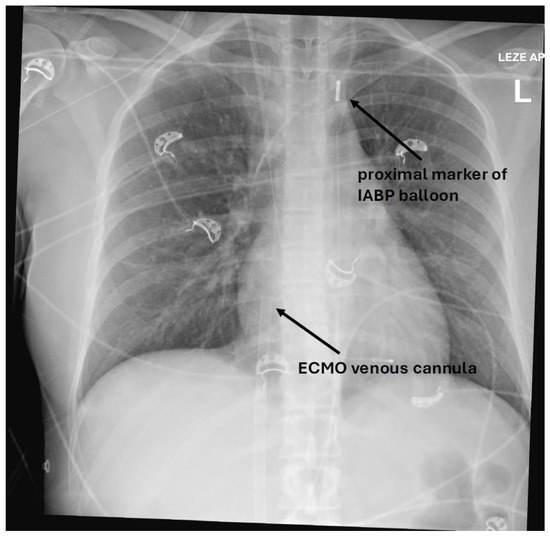

Figure 1. X-ray of a patient showing a proximal IABP balloon marker in aortic knob and an ECMO venous cannula with the tip in the right atrium.